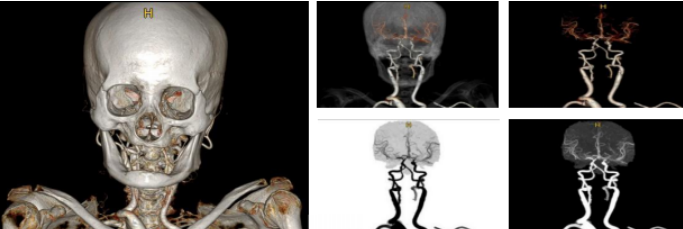

完美的图像质量

头部三维

• 剥离彻底,纤毫毕现